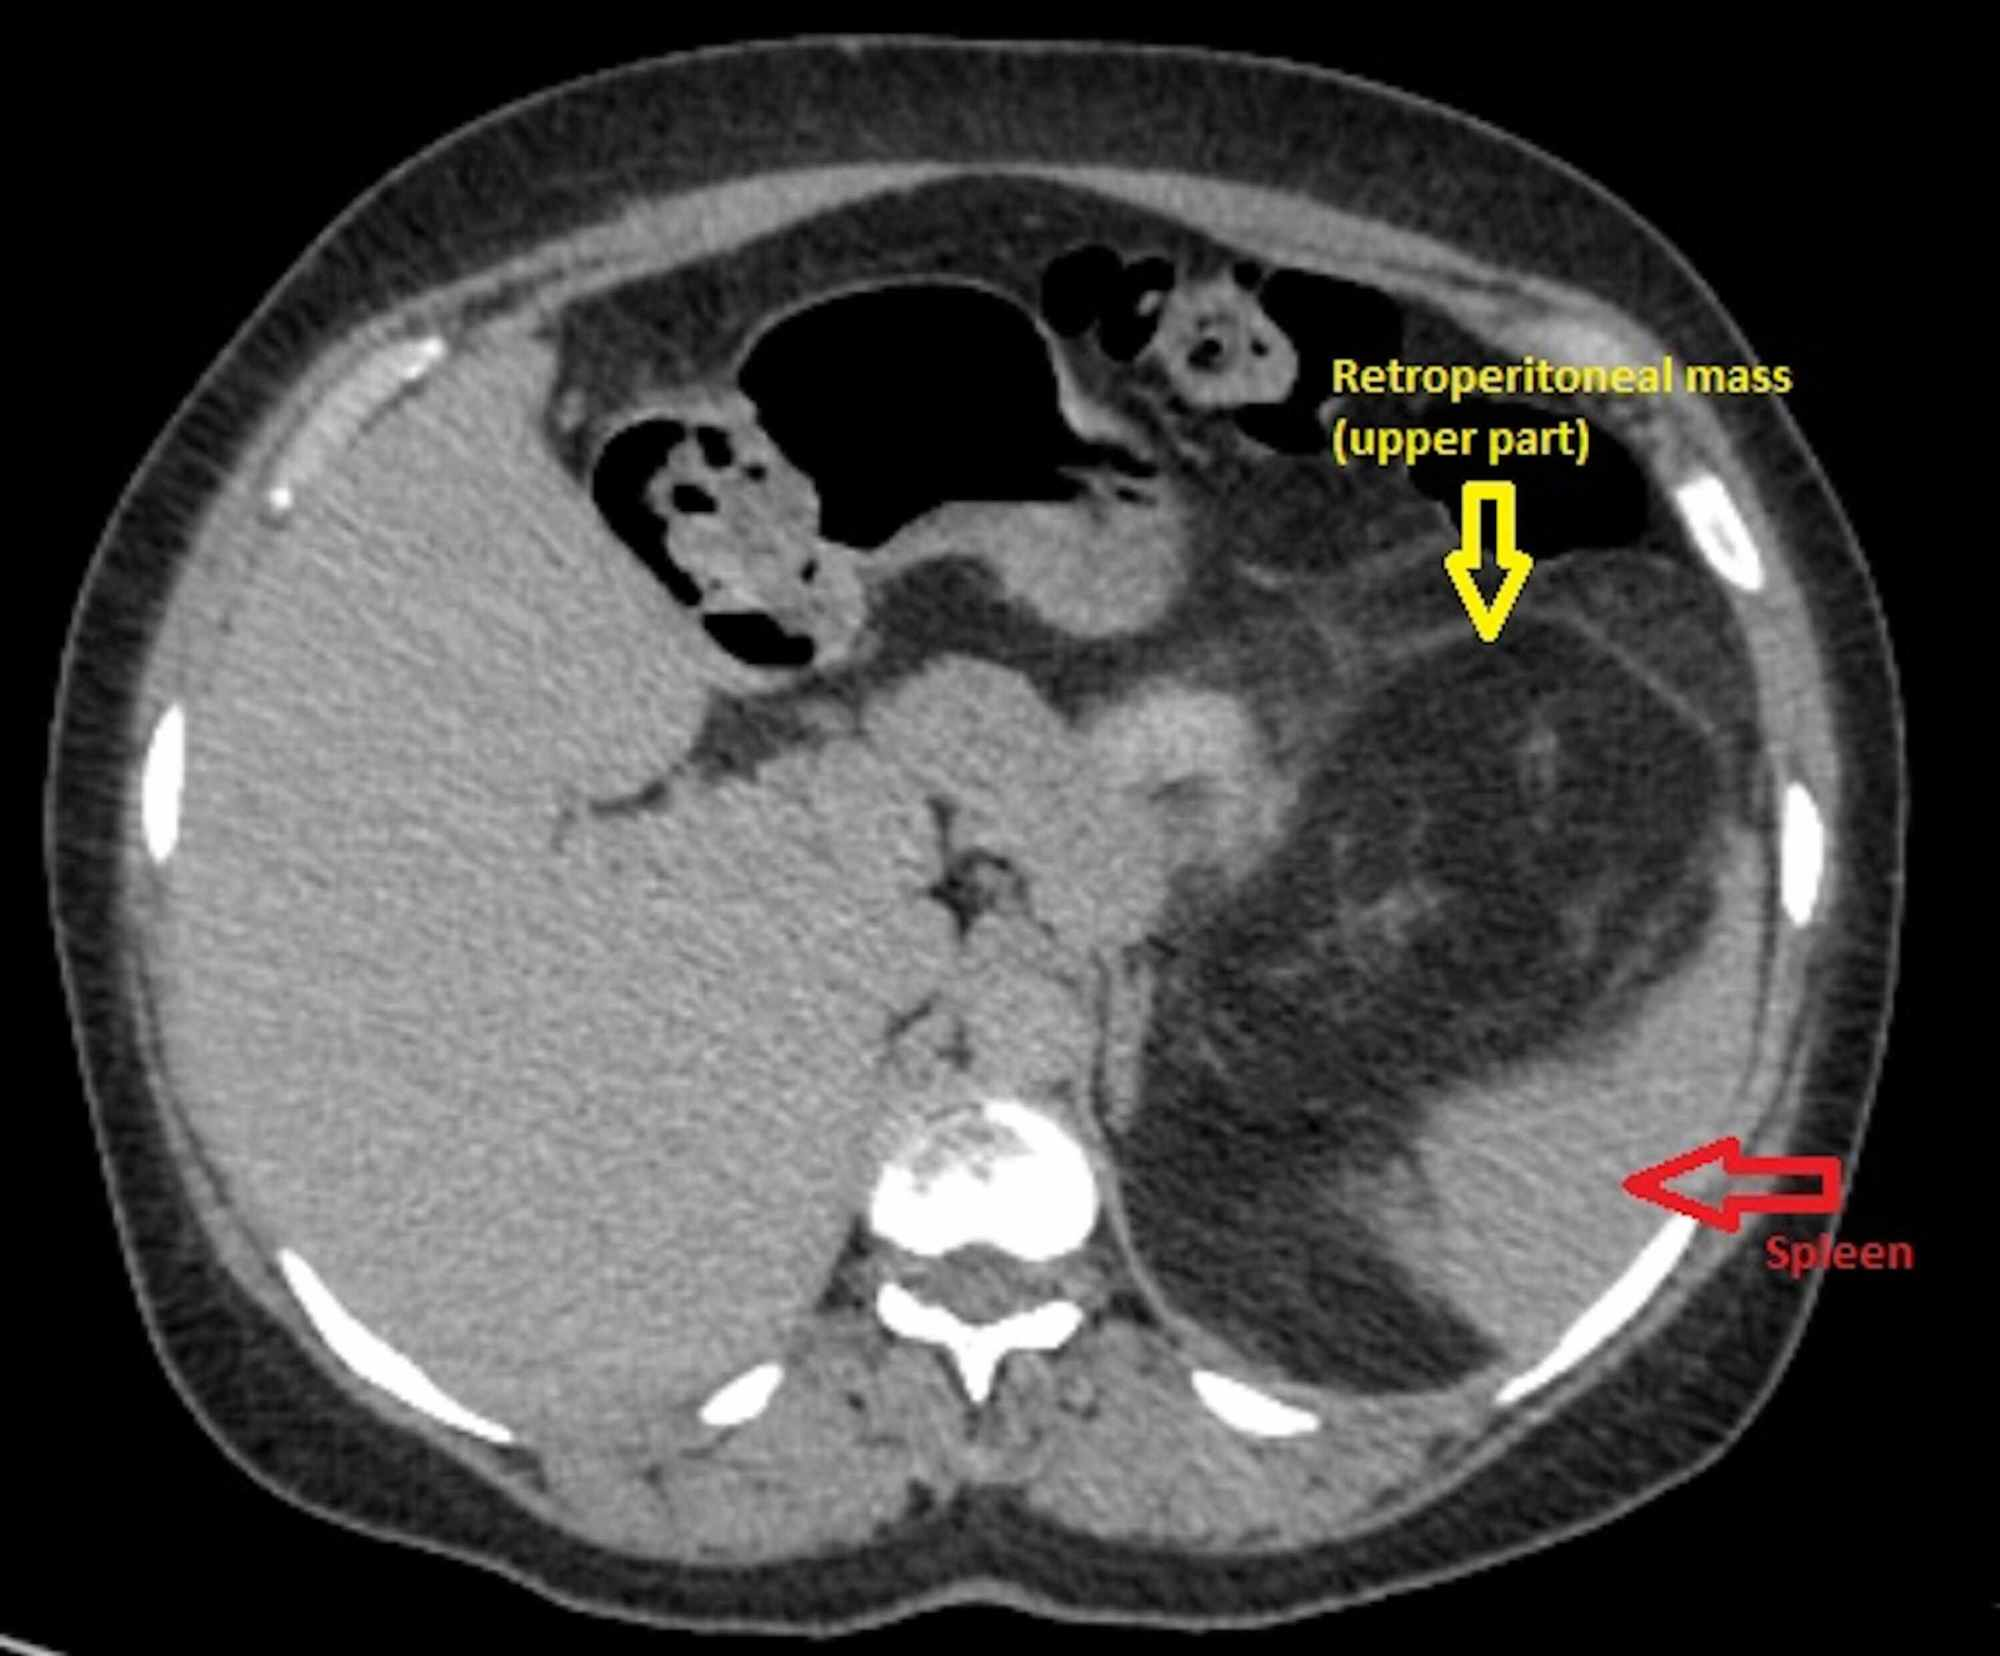

Cureus | En Bloc Resection Of A Giant Retroperitoneal Liposarcoma: A

www.cureus.com

www.cureus.com

retroperitoneal liposarcoma spleen bloc resection stomach medially laterally abdomen surgical displacing pelvis cureus